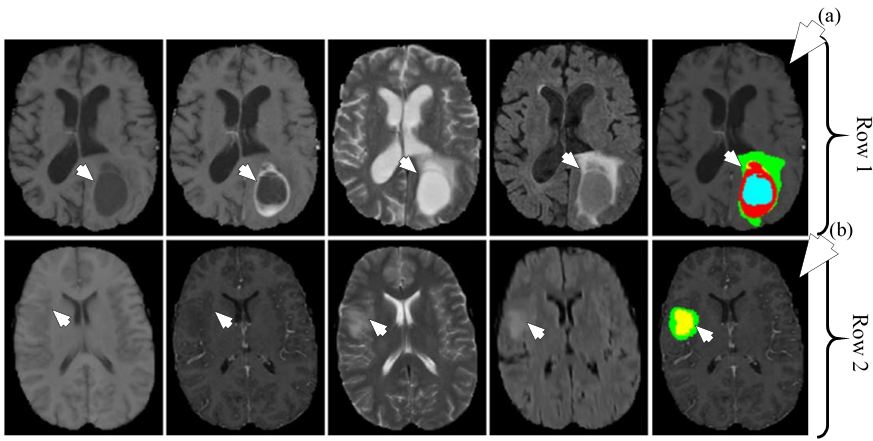

Among several types of brain tumor, Gliomas have the highest mortality rate. Gliomas are divided into two types: low grade gliomas (LGG) and high grade gliomas (HGG) with the latter being more aggressive than the former. Segmentation of Gliomas and their characterization into LGG and HGG is important for treatment, planning, and follow-up evaluation of the patients. Manual segmentation of Gliomas is tedious and error prone and therefore requires semi-automatic and automatic methods for segmentation. The detection of Gliomas is difficult because of their variable shape, structure and location. The MRI present their own set of challenges in form of intensity homogeneity and different intensity ranges along the same sequence of images and faulty acquisition scanners. Conventional methods such as ML-based techniques have been applied for segmentation but with limited success because of the above mentioned challenges. DL methods that generate their own internal features stand as an interesting alternative to the conventional methods. In this paper (48), a CNN architecture has been applied for tumor segmentation. The tumors are divided into four classes such as: edema, necrosis, non-enhancing and enhancing. The images were pre-processed before they are input into the DL system for training. The pre-processing involved normalization of the image dataset.

Two different CNNs of different depth were used for LGG and HGG. The depth of LGG CNN was lesser compared to HGG CNN as increasing depth for LGG CNN did not increase performance. The LGG CNN framework consisted of four convolutions, two max-pooling and three fully connected layers while the HGG CNN framework consisted of six convolutions, two max-pooling and three fully connected layers. Two kinds of datasets were used for the experiment such as: BRATS2013 and BRATS2015. BRATS2013 contained 65 MRI scans and BRATS2015 consisted of 274 MR scans with manual segmentation available for both. For training, 335,000 and 450,000 image patches were extracted for LGG and HGG images respectively. The dice similarity metric for complete, core and enhancing segmentation scheme was 0.88, 0.83 and 0.77 respectively. The object process diagram is shown in Figure 20. Since only 339 images were used, there is a scope of better training of the CNN with larger dataset. The segmentation output images are given in Figure 21. There is a clear potential of improvement of performance.

Figure 20DL-based system for brain tumor segmentation.

Figure 21Segmentation of HGG shown in row one and segmentation of LGG shown in row two. The different MRI sequences from left to right are T1, T1c, T2 and FLAIR. The rightmost image in row one shown by medical arrow (a) is HGG segmented image and rightmost image in row two shown by medical arrow (b) is LGG segmented image. The colors represent tumor types: green: edema, blue: necrosis, yellow: non-enhancing tumor and red: enhancing tumor (reproduced with permission from (47)).